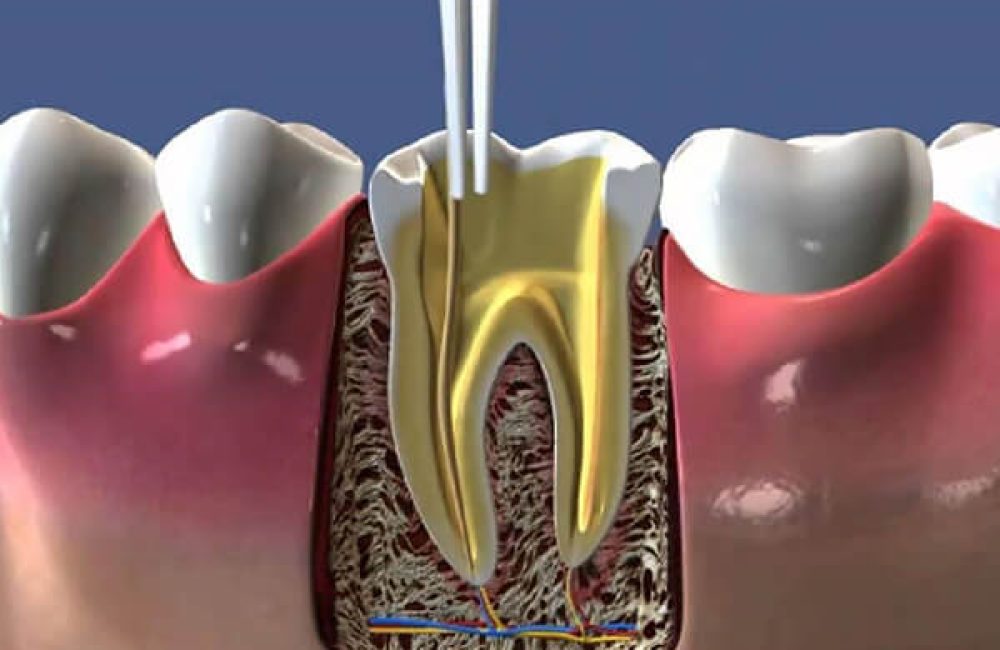

By removing the dental nerve and pulp (the tooth marrow) and cleaning the inside of the tooth, root canal treatment is performed to prevent infection of the surrounding tissues and prevent a dental abscess from causing more serious problems. It is important to perform root canal treatment as soon as possible to save the affected tooth and prevent tooth loss.

Root canal treatment is performed by a specialized dentist or endodontist. The first step is to take an X-ray. This X-ray is used to determine the condition of the dental canals and the presence of an infection in the surrounding tissues. Based on this, the dentist plans the root canal treatment to be performed. The second step is anesthesia.

The third step is to create an opening (cavity) in the tooth. Through this opening, the affected pulp, dead nerve tissue and infected particles are removed. The inside of the tooth is completely cleaned and disinfected.

The fourth step is filling the tooth. The cavity left by the removal of pulp and nerve is filled with a special rubber material. This material, called gutta-percha, is compatible with the human body and does not cause allergic reactions. This is to avoid the risk of further infections. With this step, the root canal treatment is complete.